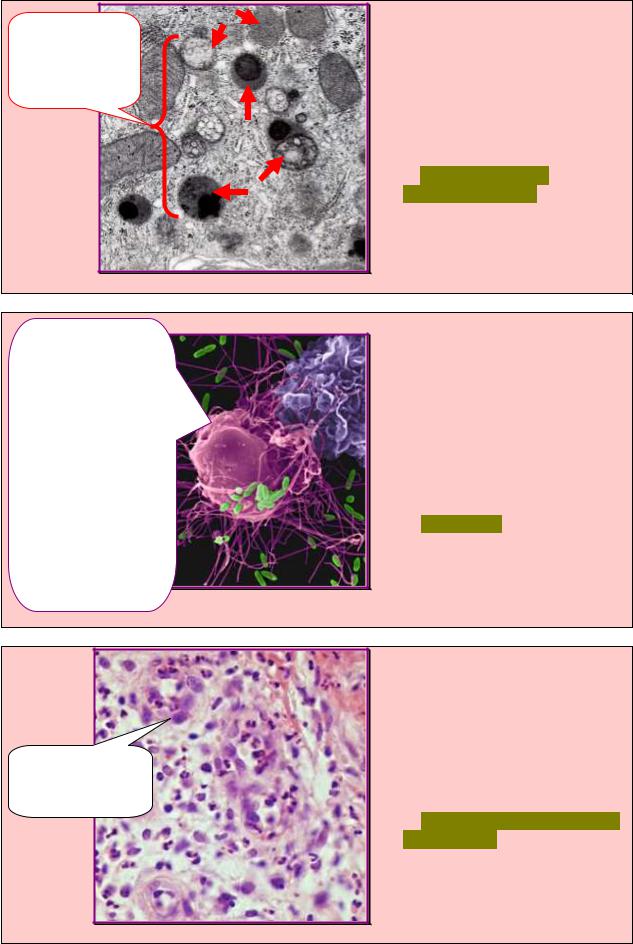

4.3. Клетки-иммигранты. Понятие о макрофагической системе организма |

(система фагоцитирующих мононуклеаров). Участие клеток в защитных реакциях |

ЗАДАНИЕ 4.30 |

В препарате выявили клетки |

соединительной |

ткани, |

обозначенные |

рис.4.30, |

обеспечивающие |

реакции |

неспецифической |

|

специфической |

защиты. |

Укажите данную группу клеток. |

А. Специализированные. |

Нейтрофилы |

Б. Сократительные. |

В. Иммигранты. |

Г. Резидентные. |

Д. Секреторные. |

Рис. 4.30 |

1.Распознавание, |

ЗАДАНИЕ 4.31 |

При сканирующей электронной |

микроскопии |

рыхлой |

соединительной ткани выявили |

клетку, |

специфические |

которой перечислены |

на рис.4.31. Назовите данную |

клетку. |

А. Макрофаг. |

Б. Фибробласт. |

В. Лейкоцит. |

Г. Эндотелиоцит. |

Д. Адипоцит. |

Рис. 4.31 |